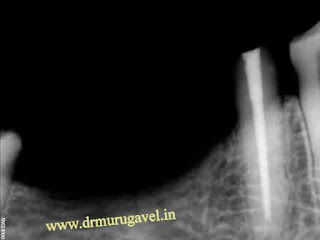

Pre treatment xray showing good quality bone in mandible

Pre treatment dental xray

Post dental implant placement